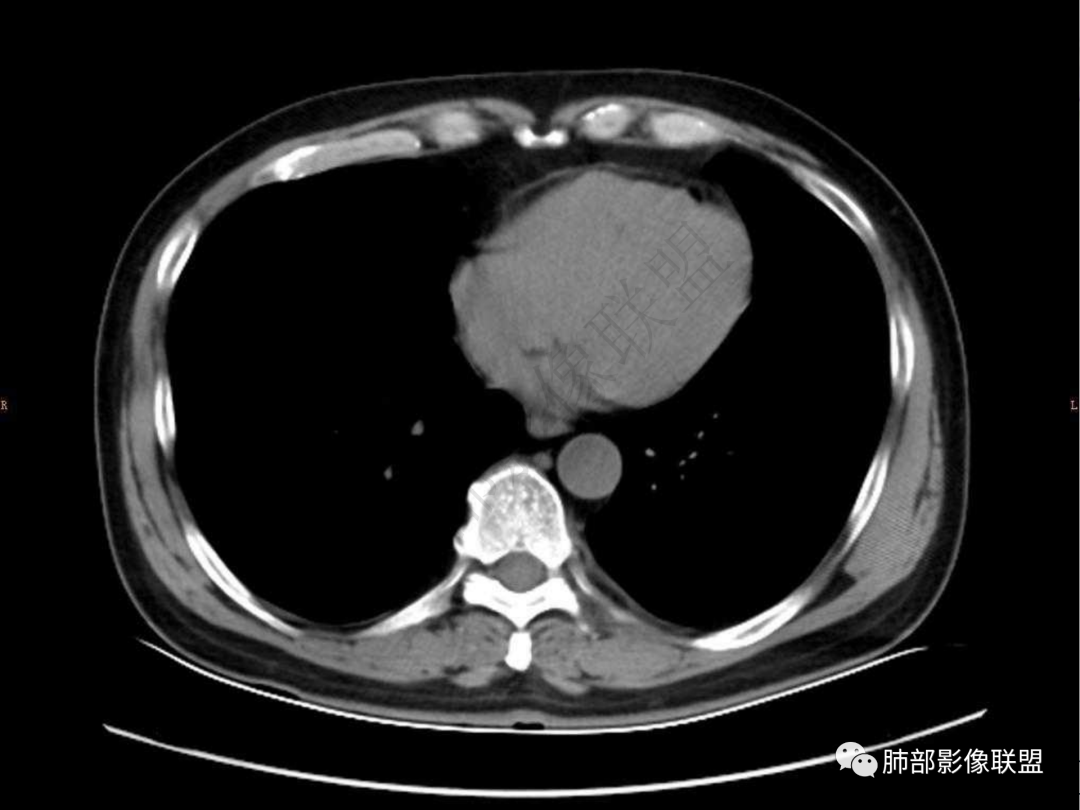

4.实性部分不均匀环形强化并显示一小范围低密度坏死区或空洞。较之肺窗,整体纵隔窗范围较小,提示病灶并不十分密实。抑或为不同时段图像。

5.双肺门及纵隔未见增大淋巴结。未见胸腔积液。

肺脓肿:可宽基底与胸膜相连,附近胸膜增厚——炎性特点

六:增强扫描:

肺脓肿:环形强化,强化较显著。如出现明显囊壁样强化甚至边缘“憩室”样突出,高度支持肺脓肿。